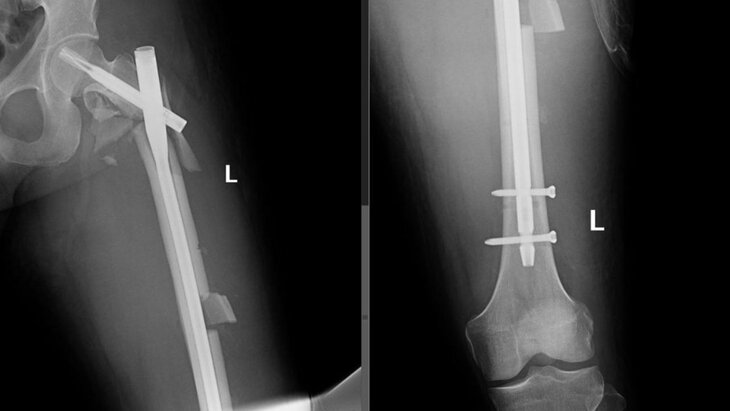

28-летний мужчина случайно выпал из окна своей квартиры. Прохожие вызвали скорую помощь. Пострадавшего доставили в медицинское учреждение с множественными травмами: переломами позвонков, открытыми переломами ребер и костей левого предплечья, закрытыми переломами таза и левой бедренной кости с повреждением бедренной артерии, а также другими повреждениями. Для его лечения потребовалась операция, в которой участвовали специалисты разных профилей.

Врачи сумели спасти ногу пациента от ампутации и устранить последствия переломов и травм. После успешной реабилитации мужчину вскоре планируют выписать.